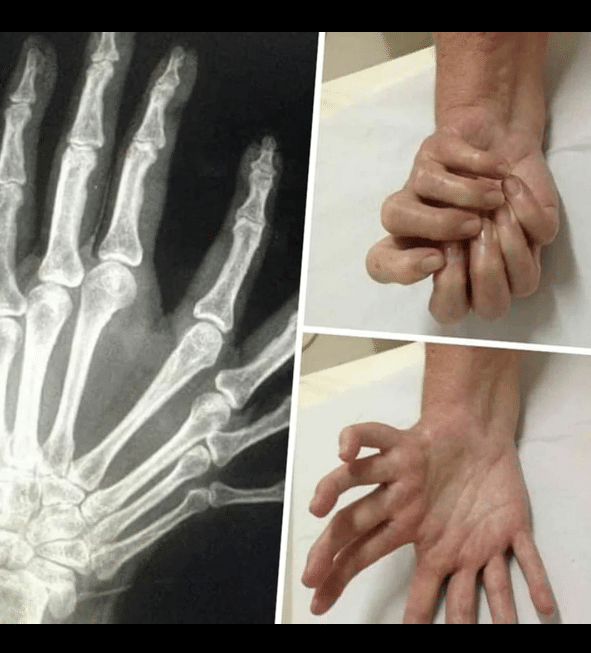

in Fotos, Imagenes interesantes Síndrome de la mano del espejo What do you think? 0 Points Upvote Downvote Leave a ReplyYour email address will not be published. Required fields are marked *Comment * Name * Email * Website Save my name, email, and website in this browser for the next time I comment.